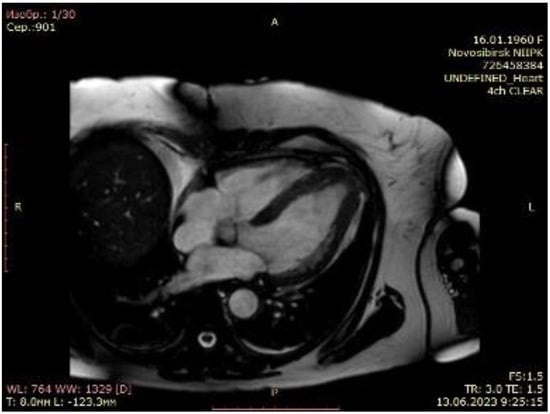

2.1. Case Scenario

2.2. Surgical Procedure